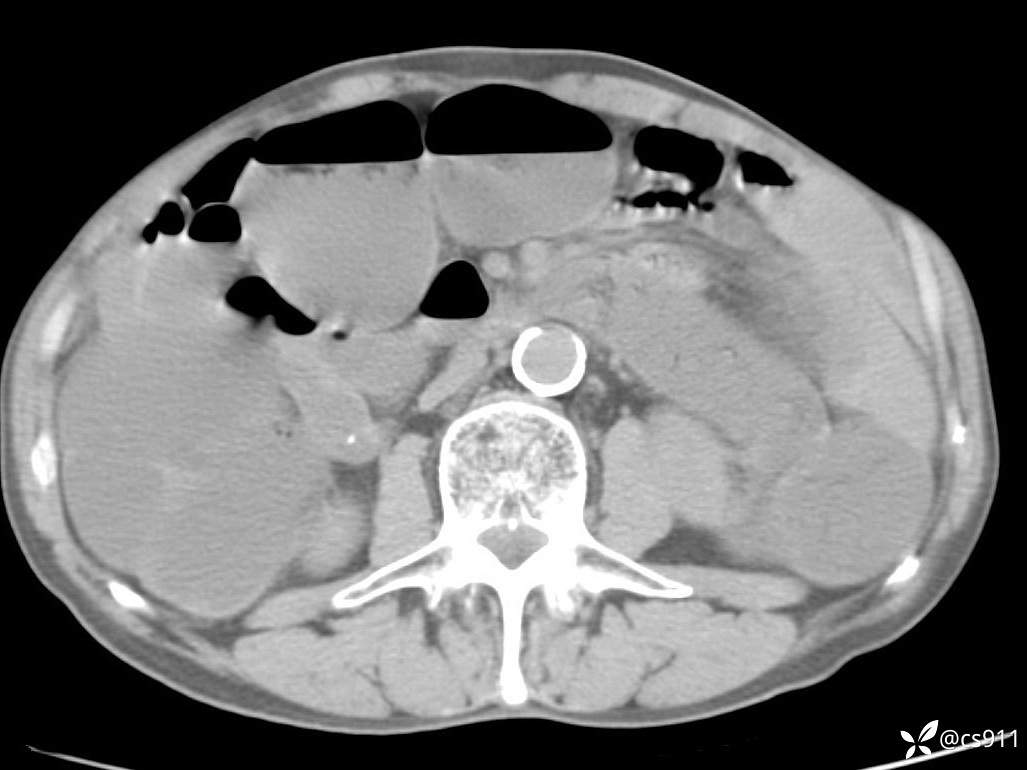

急腹症之急诊CT,原因?答案公布

男,77岁,腹痛、腹胀伴恶心呕吐1天。呕吐胃内容物,非喷射性呕吐,有咖啡色样胃内容物,诉有胃穿孔病史。查体:全腹平,下腹部压痛,全腹无反跳痛,叩诊呈浊音,移动性浊音阴性,肠鸣音减弱,1-2次/分。肛检:直肠未扪及明显肿物,可触及大量粪块。

血淀粉酶(AMY) HH 1859 U/L 35-135